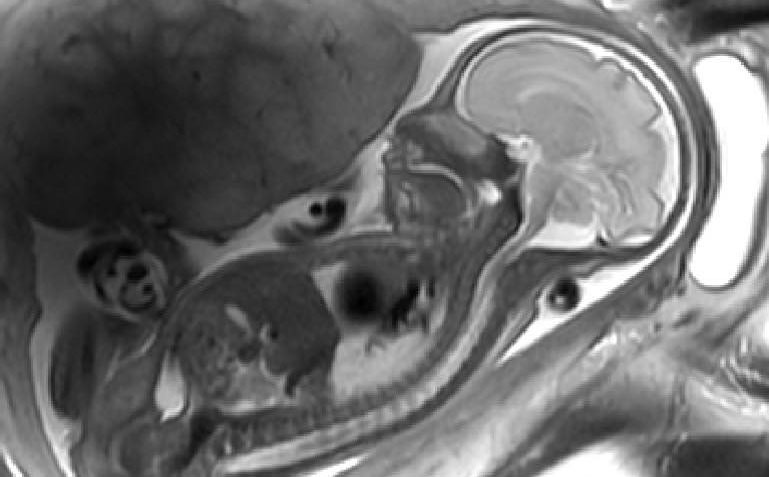

Shows the information on blood oxygen and speed of blood movement within the placenta for both a healthy pregnancy (top) and a preeclamptic pregnancy (bottom)

“I am part of a team of scientists who have used MRI to look at how blood flows through the placenta to deliver oxygen to the baby. We found that in healthy pregnancies maternal blood flows very slowly. This seems odd at first but our other measurements suggest that this is a way in which the baby can pick up nutrients and oxygen efficiently. We also found that the normal patterns of flow and oxygenation were much more variable in pre eclampsia, which can help explain why babies of pre-eclamptic pregnancies tend to be smaller and often have to be delivered before term.

Most excitingly, we also identified a completely new phenomenon which we called the ‘uteroplacental pump’. This is a contraction of the placenta and the part of the uterine wall to which it is attached, and it is not the same as the well-known Braxton Hicks contractions in which the entire uterus contracts in practice for labour. We now want to work out the purpose of these contractions but we think it might be to stop blood stagnating in parts of the placenta.”